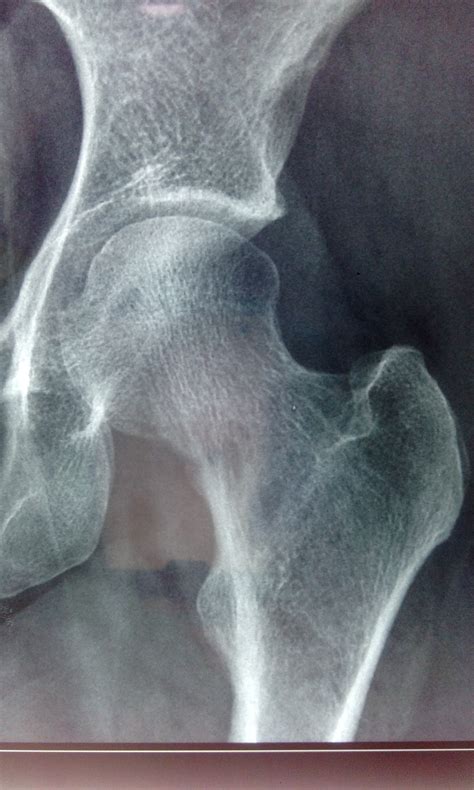

Patients Report Severe Hip Pain At Night Keeps Them Awake Daily

Causes of hip pain and treatments - Rochester Pain Solution